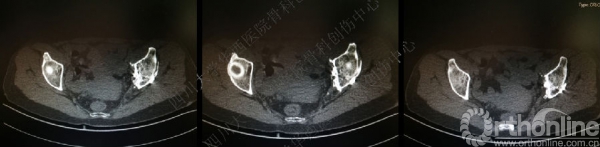

术前CT

入院后行左股骨髁上牵引,积极术前准备,做CT,证实双柱骨折的诊断。

术后CT

术后冠状位及横切面CT扫描,负重区解剖复位

术后CT也证实骨盆形态正常。